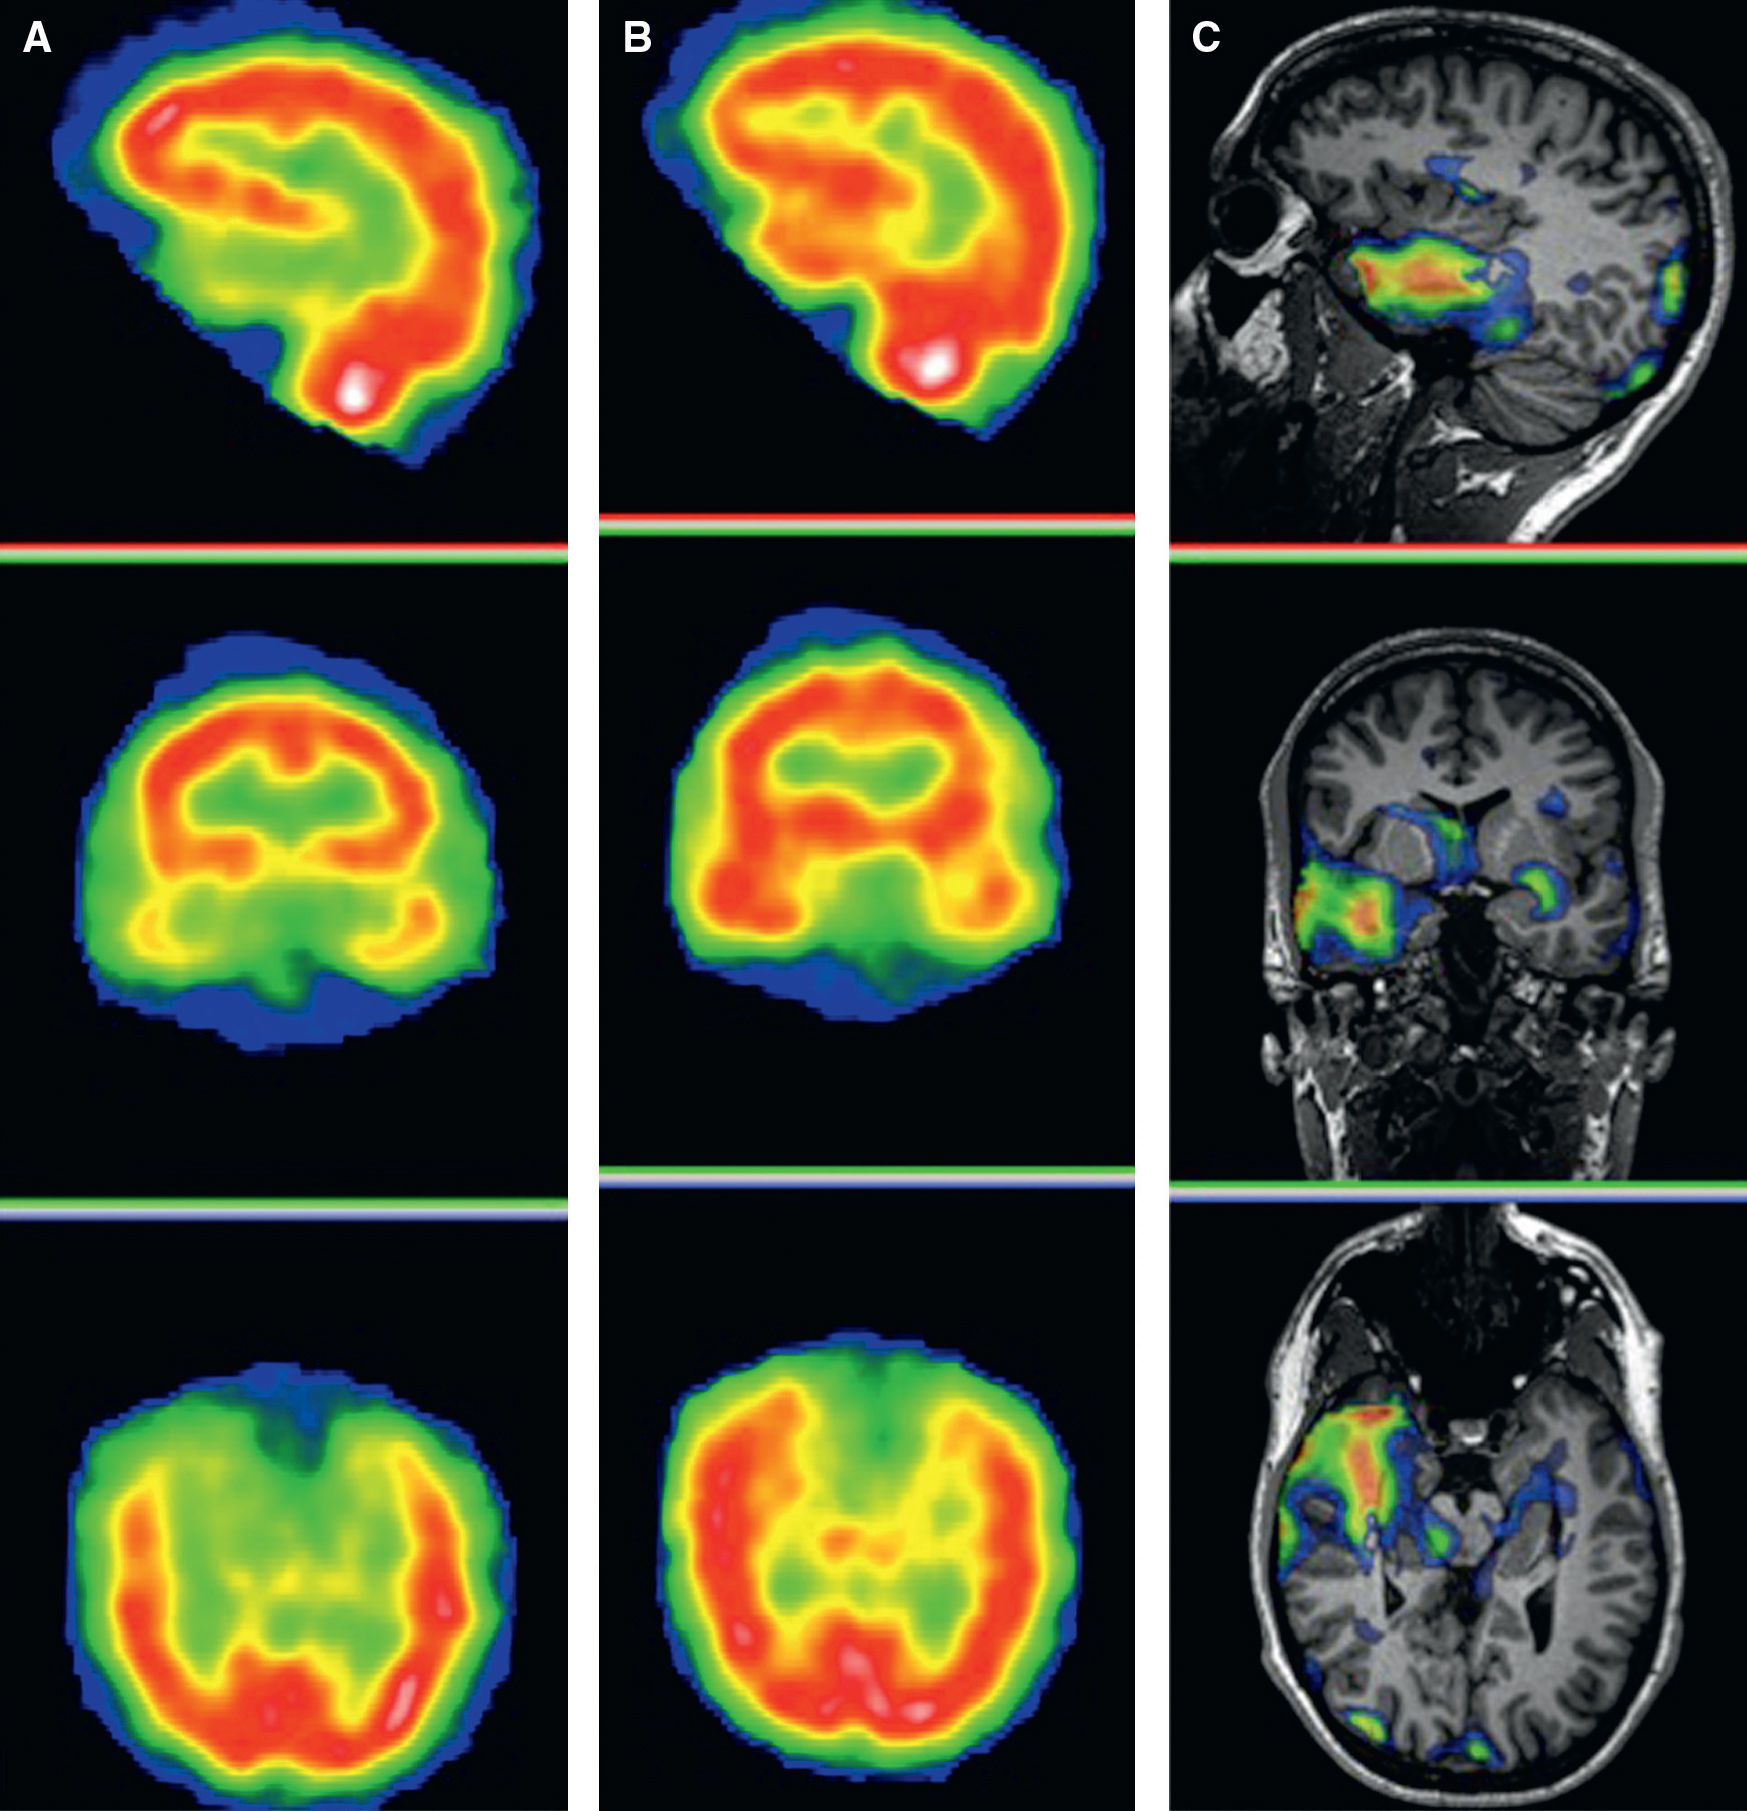

Determining the active areas of the brain during specific tasks.